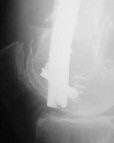

Attached are few examples from our Hospital:

Malpositioning is much too common (recurvatum, varus - valgus).

B. Fixation loosening: distal cutting of the nail, non-unions do happen (cases attached).